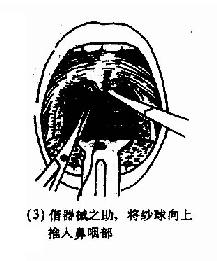

(2)后鼻孔填塞法(postnasal packing):先将凡士林纱条或消毒纱布卷迭成块形或圆锥形,长约3.5cm,直径约2.5cm,用粗线缝紧,两端各有约25cm长的双线,消毒备用。填塞时先收缩和表麻鼻腔粘膜,咽部亦喷有表面麻醉剂。用导尿管由前鼻孔沿鼻腔底部插入直达咽部,用镊子将导管从口腔拉出,导尿管尾端则留于前鼻孔外,再将填塞物上的双线系于导尿管,此时将填塞物由口腔送入鼻咽部,填塞于后鼻孔。为了减少患者痛苦,可用弯止血钳将填塞物在明视下送到悬壅垂的后上方,再将导尿管的鼻端向外拉紧。最后在前鼻孔处用一纱布球,将双线系于其上,以作固定,口腔端的线头可剪短留在口咽部,便于以后取出填塞物时作牵拉之用。后鼻孔填塞后,一般都需加行鼻腔填(图4-7)。鼻腔填塞物应于24~48小时内取出或更换,以防引起鼻窦及中耳感染等并发症。

图4-7 后鼻孔填塞法